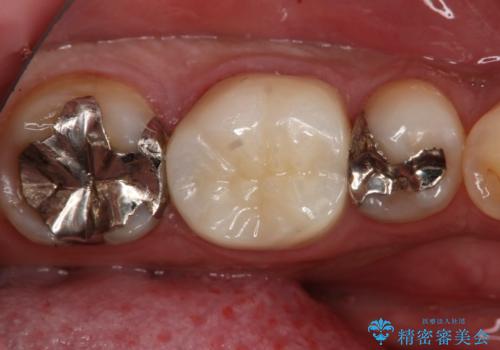

- 左上奥歯の銀歯のやり変えを希望された患者様です。

白くしたいとの事だったので形態・切削量を考慮し、セラミックインレーでの治療を計画しました。

保険材料と比較し、セラミックは劣化しない材料なので二次的な虫歯を防ぐことが出来ます。